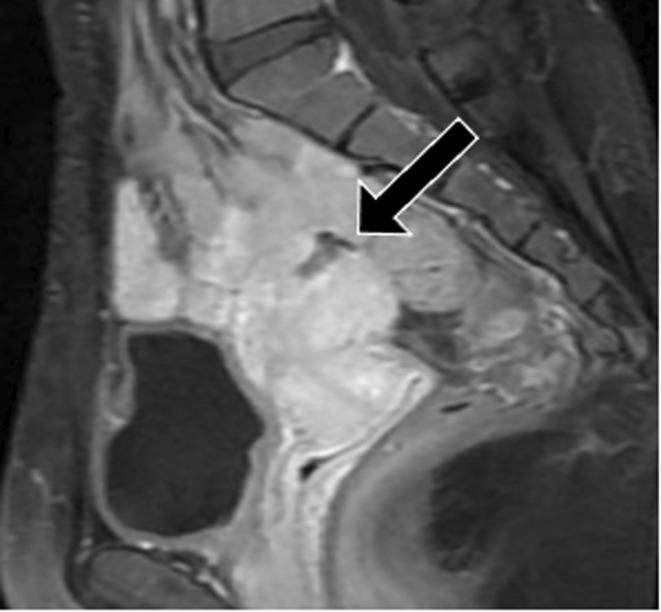

The patient's first pregnancy occurred at the age of 33 years, and a cesarean section was performed at a previous hospital by a transverse uterine fundal incision with double‐layer closure of the uterine muscle due to placenta previa, in which the placenta covered the anterior uterine wall. Sagittal T1‐weighted magnetic resonance imaging (MRI) with contrast revealed a cesarean section scar defect at the uterine fundus 12 months postpartum (Figure 1). Considering the risk of uterine rupture, it was recommended that the patient did not become pregnant in future. The couple wished for a second child, and the patient conceived by in vitro fertilization at another clinic at 38 years.

FIGURE 1.

Sagittal T1‐weighted magnetic resonance imaging with contrast at 12 months postpartum showed a cesarean section scar defect at the uterine fundus (arrow)